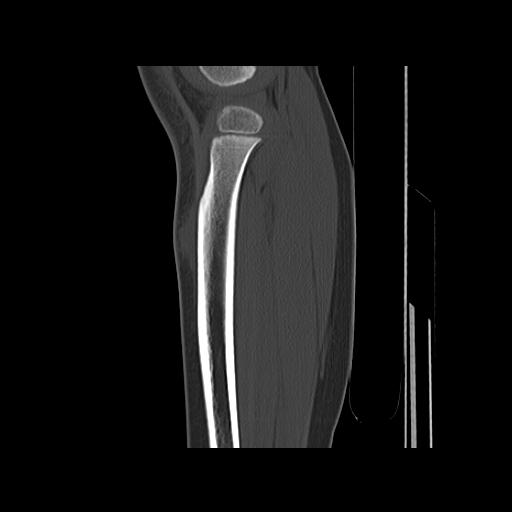

标题: PED0931:男,5岁,发现双小腿软组织肿块1年,质地中等,无 [打印本页]

标题: PED0931:男,5岁,发现双小腿软组织肿块1年,质地中等,无

考虑多发性神经纤维瘤.

考虑多发性神经纤维瘤.支持